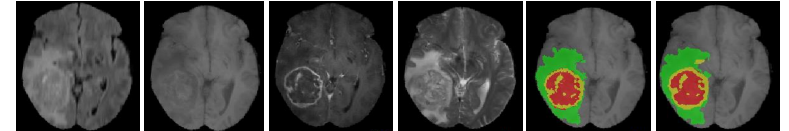

The visualization of the validation set prediction is illustrated in Figure 3:

Figure 3: All the four modalities of the brain tumor visualized with the Ground-Truth and Predicted segmentation of tumor sub-regions for BraTS 2019 crossvalidation dataset. Red label: Necrosis, yellow label: Edema and Green label: Edema.